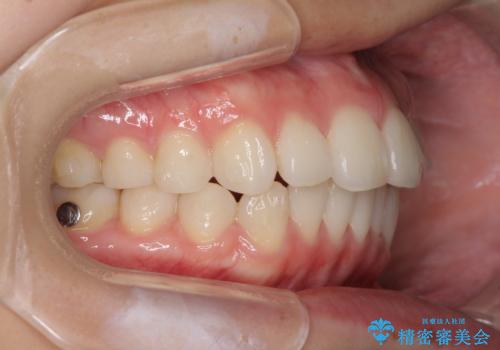

- デコボコと飛び出した前歯を治したいとのことで来院された患者様です。

ゴムかけを活用して上顎歯列全体を後方移動し、IPR(歯と歯の間を削る)によってデコボコが解消するように設計し、インビザラインにより治療を行うこととしました。

後方移動に際し、上下顎の親知らずは4本とも抜歯することとしました。

毎日しっかりと装着してくださったので、概ねシミュレーション通りに歯を移動させることができました。

治療前には接触することのなかった上下の前歯が接触するようになり、食事の際前歯でものをかみ切れるようになりました。

気にしていた口元の印象が改善され、患者様には大変満足していただきました。